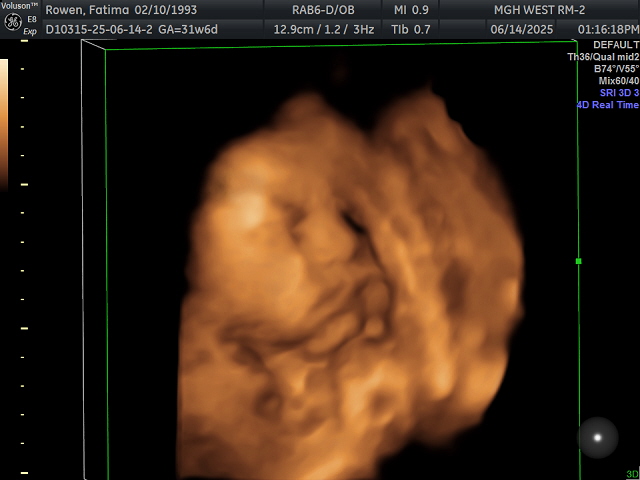

I was able to see his chubby cheeks and cute lips. I saw him yawn and play with his foot by grabbing it. It’s so reassuring to see that he’s doing well inside me. It helps during those rough moments—like throwing up or dealing with heartburn—when I picture his cute face in my head. It helps me push through the sleepless nights. We also saw him moving around, which explains a lot of what I’ve been feeling in my belly.

Like every single ultrasound, no matter how much I moved around, his face was really hard to capture. He always smushes his face against the placenta, and I guess he’s just super comfy there haha. At least I got a little peek at his chubby face though. At the end of the session, since Katya loved the unicorn plushie, we decided to put his heartbeat sound inside the unicorn as a keepsake. Katya seems to half understand that it’s her little brother’s heartbeat now. She occasionally hugs it and tells me it’s her brother, which is so sweet. I cannot wait for Katya to meet him in August!